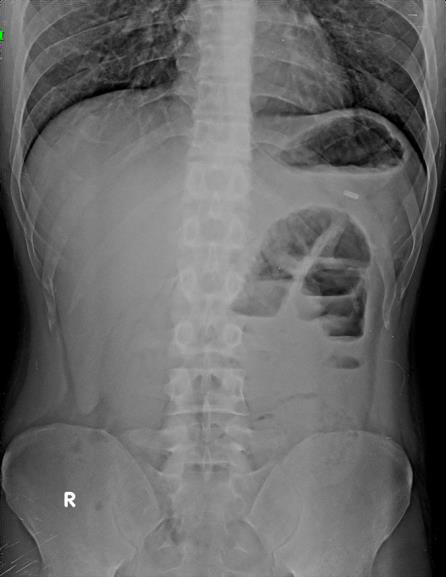

complaints in the past. Patient was advised erect abdominal

radiogram [Figure 1] which revealed a few localized dilated bowel

loops with air–fluid levels in the left upper paramedian region,

suggestive of localized small bowel obstruction without evidence of

Pneumoperitoneum. For further evaluation, a contrast-enhanced

Figure 1:Erect abdominal radiograph demonstrates localized dilatation of a

few small-bowel loops in the left upper paramedian region, showing multiple

air–fluid levels consistent with small-bowel obstruction.